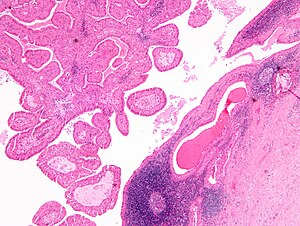

| LM | papillae with a two rows of pink (eosinophilic) epithelial cells (with cuboidal basal cells and columnar luminal cells), fibrous capsule, cystic space filled with debris, lymphoid stroma |

- Papillae (nipple-shaped structures) with a two rows of pink (eosinophilic) epithelial cells (with cuboidal basal cells and columnar luminal cells) - key feature.

- Fibrous capsule - pink & homogenous on H&E stain.

- Cystic space filled with debris in situ (not necrosis).

- Lymphoid stroma.

The sections show a cystic tumour with lymphoid tissue associated with benign salivary gland tissue. The lymphoid tissue is composed of small cells and forms morphologically unremarkable follicles. The cyst-lining epithelium has a bilayered appearance and is composed of cells with abundant eosinophilic cytoplasm and nucleoli. The tumour focally extends to the edge of the tissue (ink present on tumour).